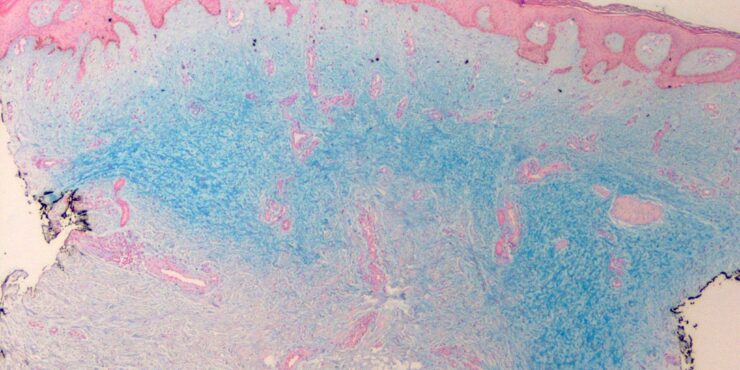

Poroma=شزن=تورم بسبب إفراز غدي POROMA The term poroma refers to a group of rare cutaneous appendage tumors composed of cells (cuticular and poroid cells) similar to those of the acrosyringium. Poromas are traditionally subcategorized histopathologically based on their location in relation to the epidermis into three main variants; namely, hidroacanthoma simplex, eccrine poroma, and […]